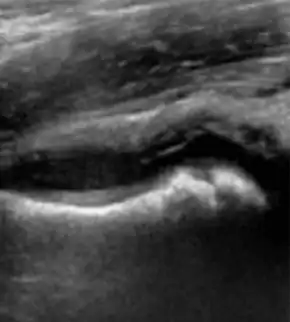

An ultrasound scan of the hip can easily demonstrate fluid inside the joint capsule (Fabella sign), although this is not always present in transient synovitis.[8][16] However, it cannot reliably distinguish between septic arthritis and transient synovitis.[17][18] If septic arthritis needs to be ruled out, needle aspiration of the fluid can be performed under ultrasound guidance.[19] In transient synovitis, the joint fluid will be clear.[7] In septic arthritis, there will be pus in the joint, which can be sent for bacterial culture and antibiotic sensitivity testing.